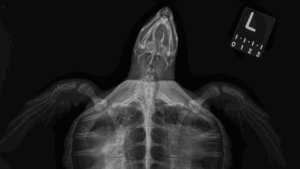

Cold-stunned sea turtles

Each fall, hundreds of cold-stunned sea turtles arrive at the Aquarium’s Sea Turtle Hospital at our Animal Care Center in Quincy, MA, after washing ashore from frigid Cape Cod Bay.

Every turtle receives intake radiographs upon arrival, which help Aquarium veterinarians diagnose injuries and illness. Cold-stunned turtles often develop pneumonia or, in some cases, bone infections such as osteomyelitis, both of which are visible on the radiographs.

Follow-up radiographs over the next several weeks allow veterinarians to track healing and monitor changes in the lungs and bones as the turtles recover. Amid the seriousness of treatment, the images sometimes reveal lighter details too, like bits of crab in a Kemp’s ridley sea turtle’s digestive tract, a favorite snack of theirs.